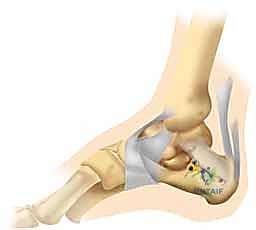

المفصل تحت الكاحل (Subtalar Joint)

تكمن الخطورة الحقيقية عندما يمتد الكسر إلى داخل "المفصل تحت الكاحل". هذا المفصل مسؤول عن حركتي الانقلاب الداخلي (Inversion) والانقلاب الخارجي (Eversion) للقدم، وهي الحركات التي تسمح لنا بالمشي على الأسطح غير المستوية والحفاظ على توازننا.

عندما يتعرض هذا المفصل للكسر، فإن الإصابة تتعدى مجرد "عظم مكسور" لتشمل تدميراً كاملاً للهندسة الميكانيكية للقدم. يؤثر هذا النوع من الكسور بشكل مباشر وعنيف على طريقة المشي، وبدون علاج دقيق وموجه من خبير مثل الأستاذ الدكتور محمد هطيف، قد ينتهي الأمر بالمريض إلى ألم مزمن، تيبس مفصلي، وعرج مستمر.

يُعد "النهج الجانبي الموسع" تقنية جراحية معقدة تتطلب مهارة استثنائية وإلماماً تشريحياً دقيقاً، وهو ما يتقنه الأستاذ الدكتور محمد هطيف ببراعة. يتيح هذا النهج رؤية شاملة وكاملة للجدار الجانبي لعظم الكعب والمفصل تحت الكاحل، مما يسمح للجراح بإعادة تجميع الشظايا العظمية بدقة متناهية كما لو كان يجمع قطع "الأحجية" (Puzzle).